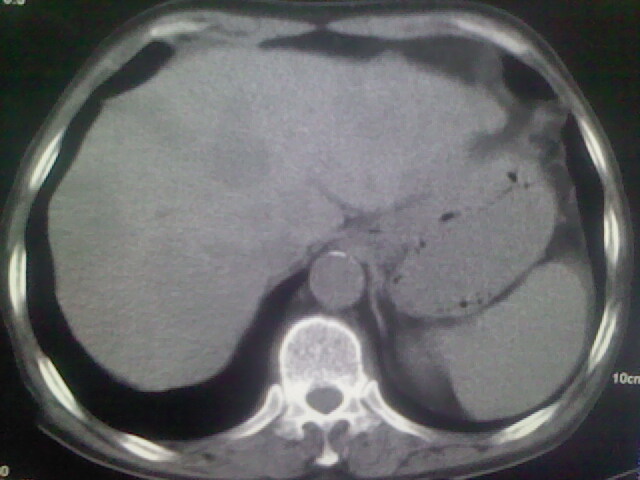

男,70y,胃占位,重度贫血,黑便3月余,伴恶心,纳差,乏力

肝内弥漫低密度---转移瘤

右上肺周围型肺癌,肝内多发低密度影---转移瘤?建议增强;胃壁明显增厚.

1)考虑右肺上叶周围型肺癌并纵隔及右颈部淋巴结转移,肝脏多发性转移。2)肺气肿。3)冠状动脉及主动脉钙化。